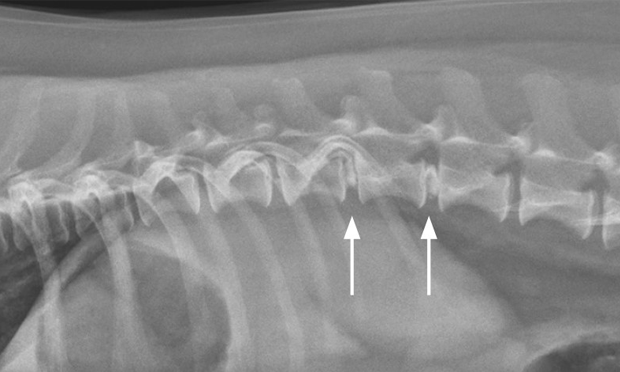

Intervertebral Disc Disease in Dogs Southeast Veterinary Neurology

A Review of Cervical IVDD SEVN Webinar Series